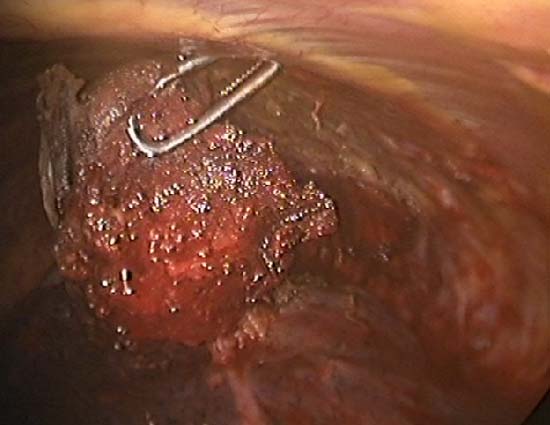

The TissueLink device does not perforate or cut into tissue (in contrast to conventional electrocautery). Instead, the surface of the tissue is painted with the device, which first coagulates and then shrinks the lung tissue (Figure 3). The surgeon then divides the coagulated tissue with scissors (Figure 4). Compared with conventional electrocautery, the TissueLink device usually leaves the resection bed more hemostatic and pneumostatic.